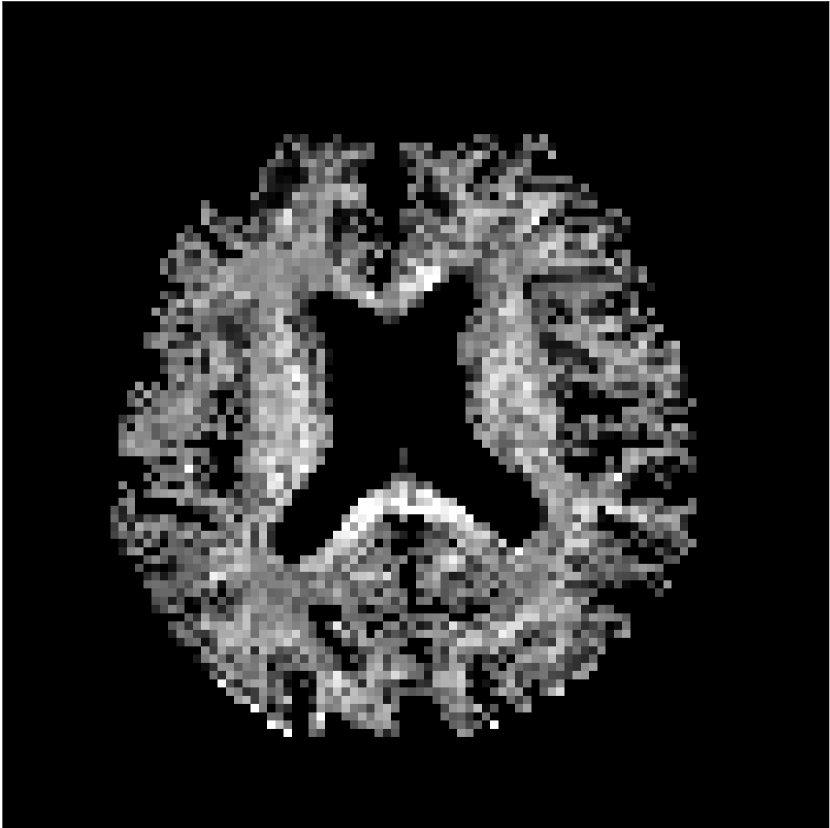

Figure 8 shows examples of non-diffusion-weighted images before and after processing. The raw images (Raw) served as the input for the magnitude deep learning (MCNN) and complex deep learning (CCNN) methods.

Raw

MCNN,

MCNN Resid.,

CCNN,

CCNN Resid.,

No PF

5/8 PF

Both methods remove artifacts, but the MCNN method allows residual rippling artifacts to pass through in the presence of partial Fourier. These rippling artifacts are not present in the CCNN method.